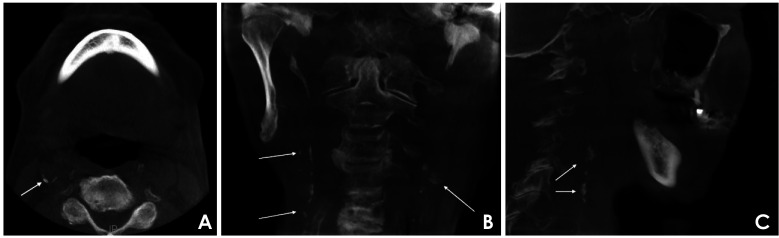

目的:本研究旨在评估偶发性血管钙化样影像学表现与自我报告的医疗数据之间的相关性,并评估报告的诱发因素与使用锥形束计算机断层扫描(CBCT)数据的影像学表现之间的关系。材料和方法:对188名男性和203名女性的391张CBCT扫描进行匿名分析,以确定颅外颈动脉和颅内颈动脉钙化(ECAC和ICAC分别)和Mönckeberg内侧硬化(MMS)的迹象。根据患者自述的病史将其分为4组。描述性统计用于评估数据,随后通过简单的单变量逻辑回归分析进行验证。结果:在391张CBCT扫描中,23.27%显示ECAC, 42.71%显示ICAC, 1.8%显示MMS。结论:这些发现强调了对牙科患者进行全面治疗前病史评估的重要性,特别是当在CBCT成像上观察到血管钙化样征象时。

Results: Among the 391 CBCT scans reviewed, 23.27% exhibited ECAC, 42.71% demonstrated ICAC, and 1.8% showed MMS. Statistical analysis revealed a significant correlation (P<0.05) between both ECAC and ICAC and self-reported predisposing factors-including hypertension, cardiovascular disease, dyslipidemia, diabetes mellitus, and sleep apnea/chronic obstructive pulmonary disease-with notable differences among the study categories (P<0.05). In addition, a strong correlation (P<0.001) was found between the presence of ECAC, ICAC, and MMS and increasing age. Men were significantly more susceptible to ECAC than women (P<0.05).